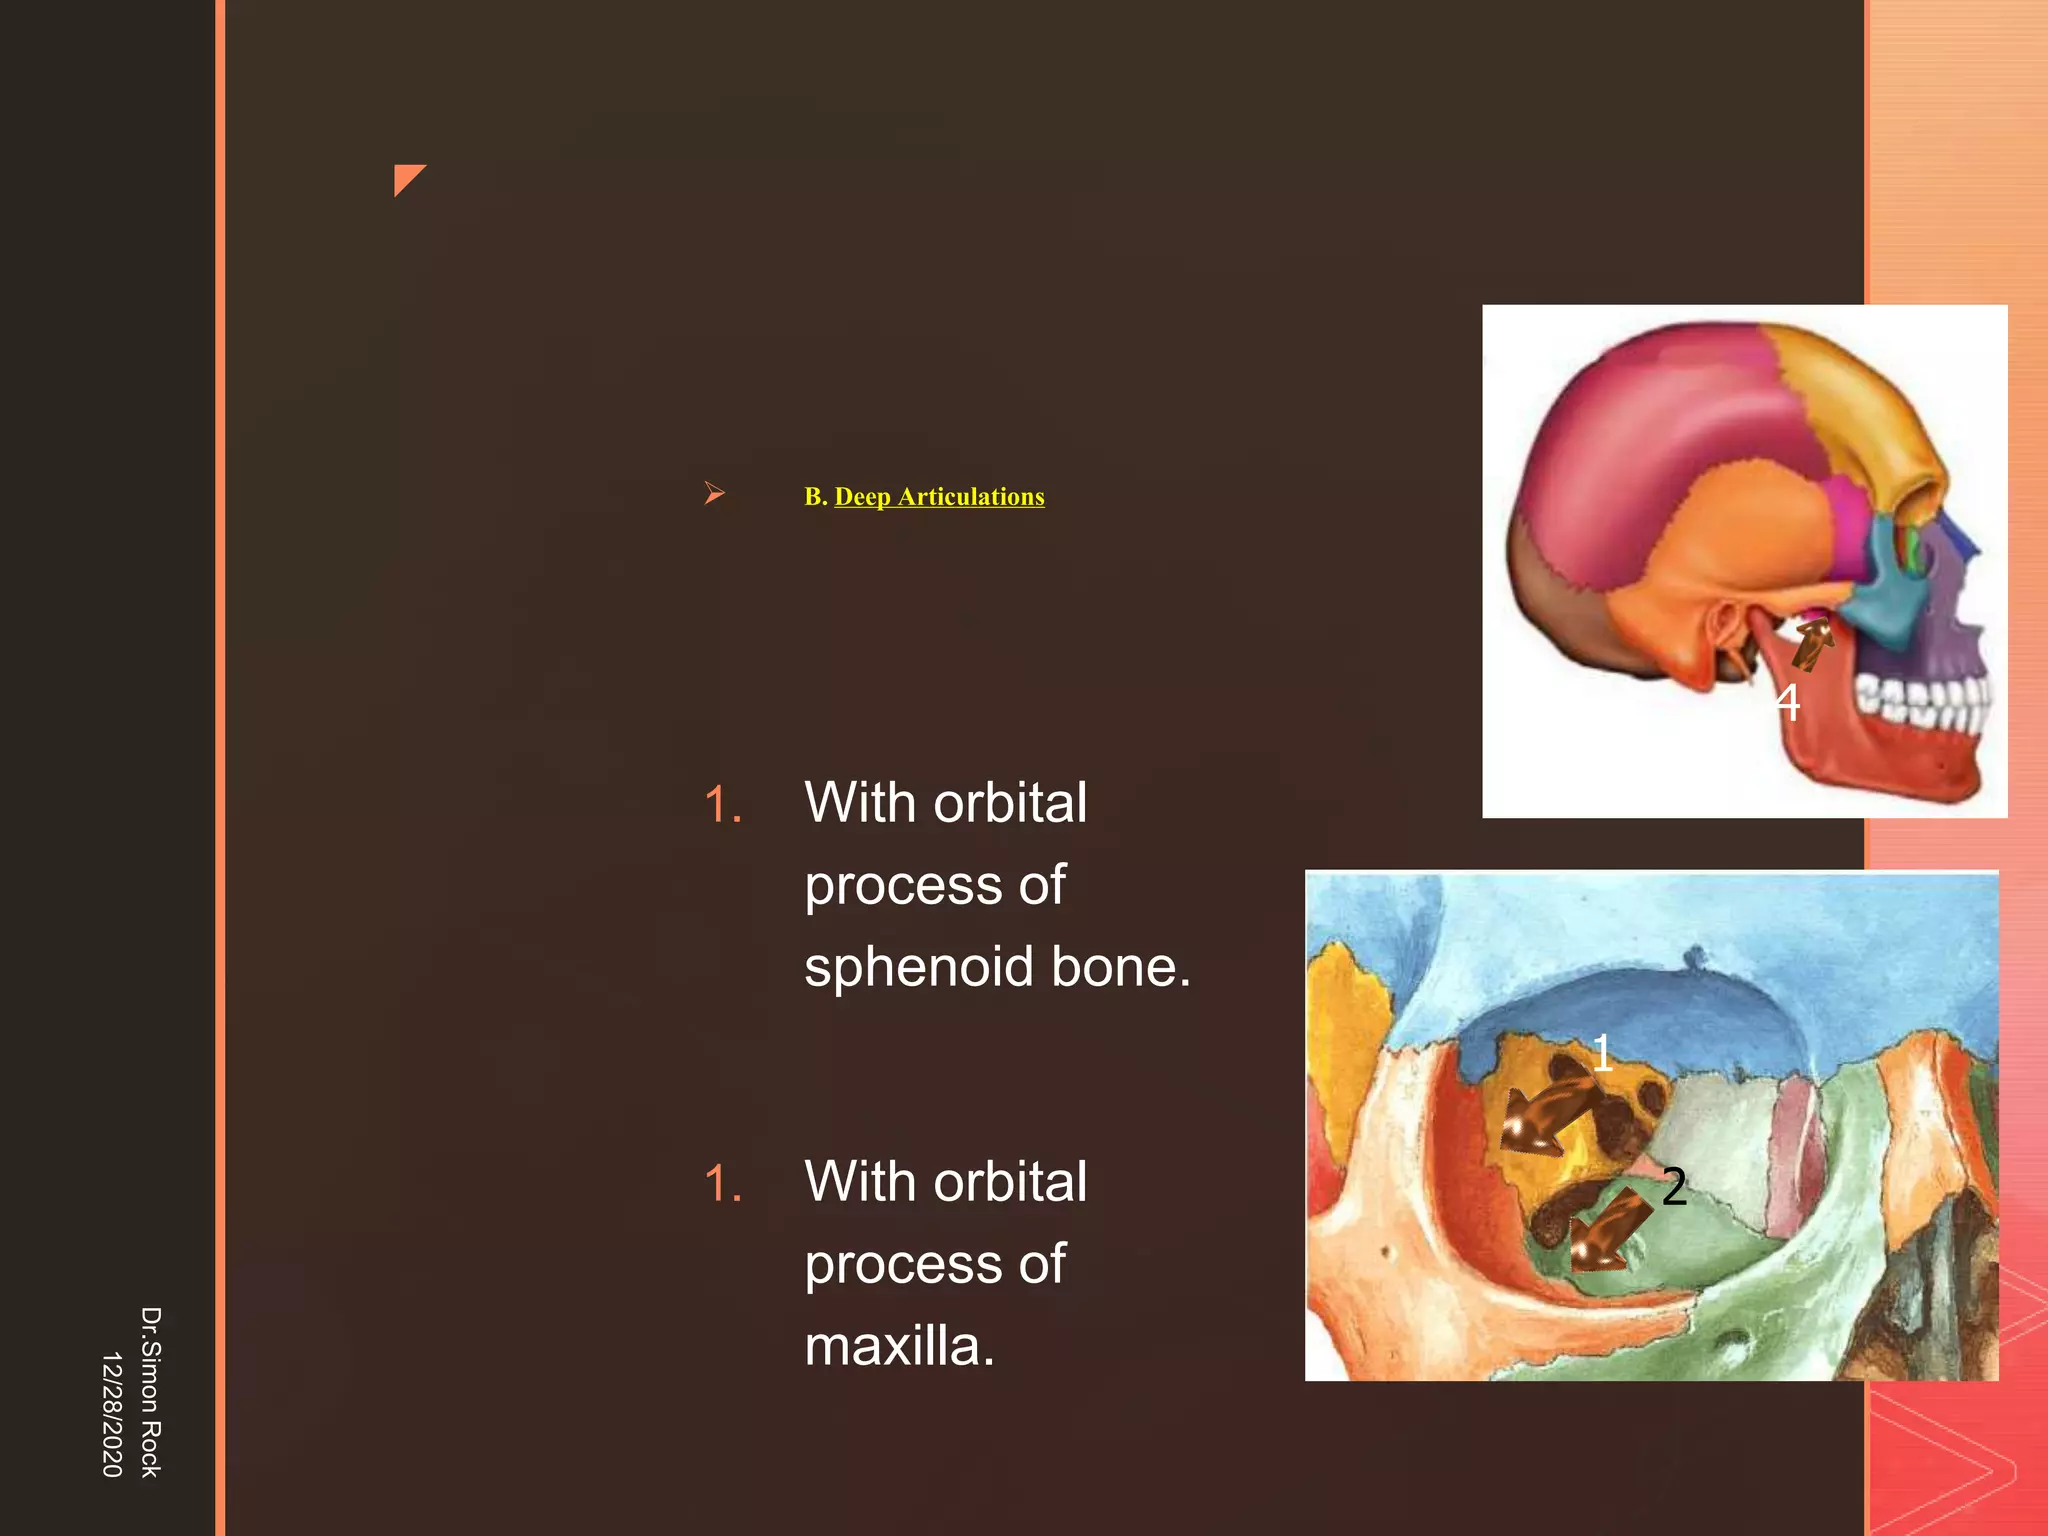

This document discusses the anatomy and fractures of the zygomatic bone. It notes that the zygoma forms the cheekbone and articulates with several other facial bones. Zygomatic fractures most commonly occur in the arch or body due to blunt trauma. Diagnosis involves checking for diplopia, ecchymosis, and other signs of orbital or facial bone involvement. Treatment may involve closed or open reduction based on the severity of displacement. Closed reduction techniques try to elevate the bone back into position without surgery, while open reduction requires surgical exposure and fixation of the fracture site.